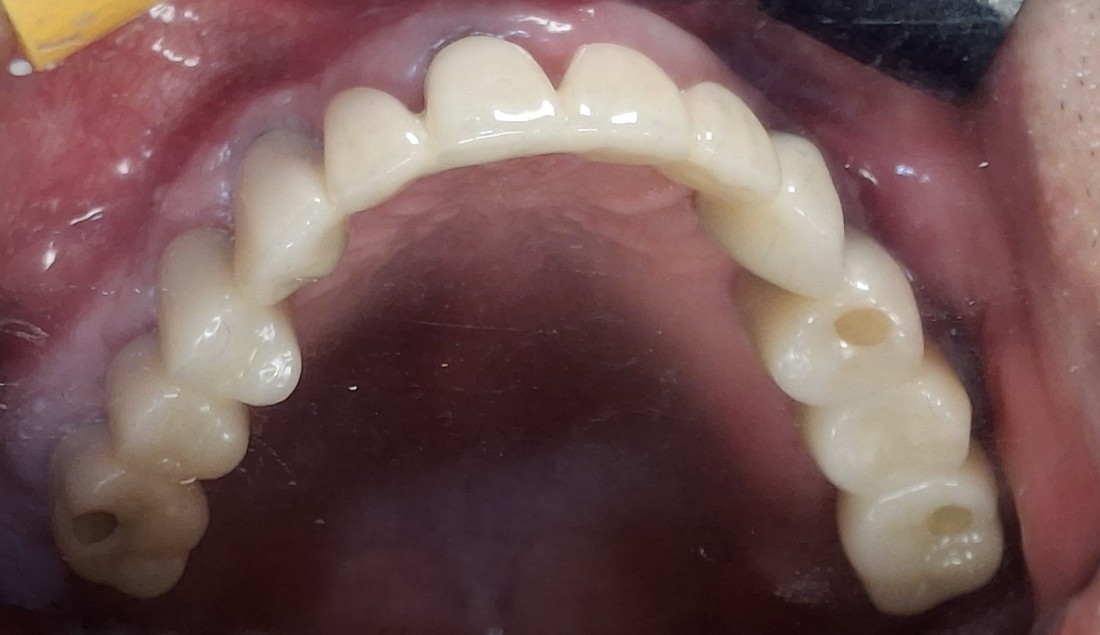

수완동 임플란트 치과는

자체 치아기공소를 운영하고 있습니다.

대표원장인 제가 직접

치아기공소의 보철물 퀄리티를

관리하고 있기 때문에,

무엇보다도

< 예쁘게, 잘 씹어지는 >

수완동 임플란트를 약속드릴 수 있습니다.

잘 관리하면 반영구적으로 사용할 수 있는

임플란트이기 때문에

특히 자연치아보다 더 자연스러운

아름다운 임플란트를 완성하는

수완동 임플란트 치과입니다.

수 백개의 임플란트 전/후 케이스 사진을

홈페이지에 공유하고 있습니다.

전체 임플란트부터

신경쓰이는 앞니 임플란트,

20대 / 30대 임플란트 케이스부터

80대가 넘는 분들의 케이스까지

정말 다양한 모든 케이스를 보유하고 있습니다.

다양한 각도의 임플란트 식립 전/후 사진으로

실력에 자신있는